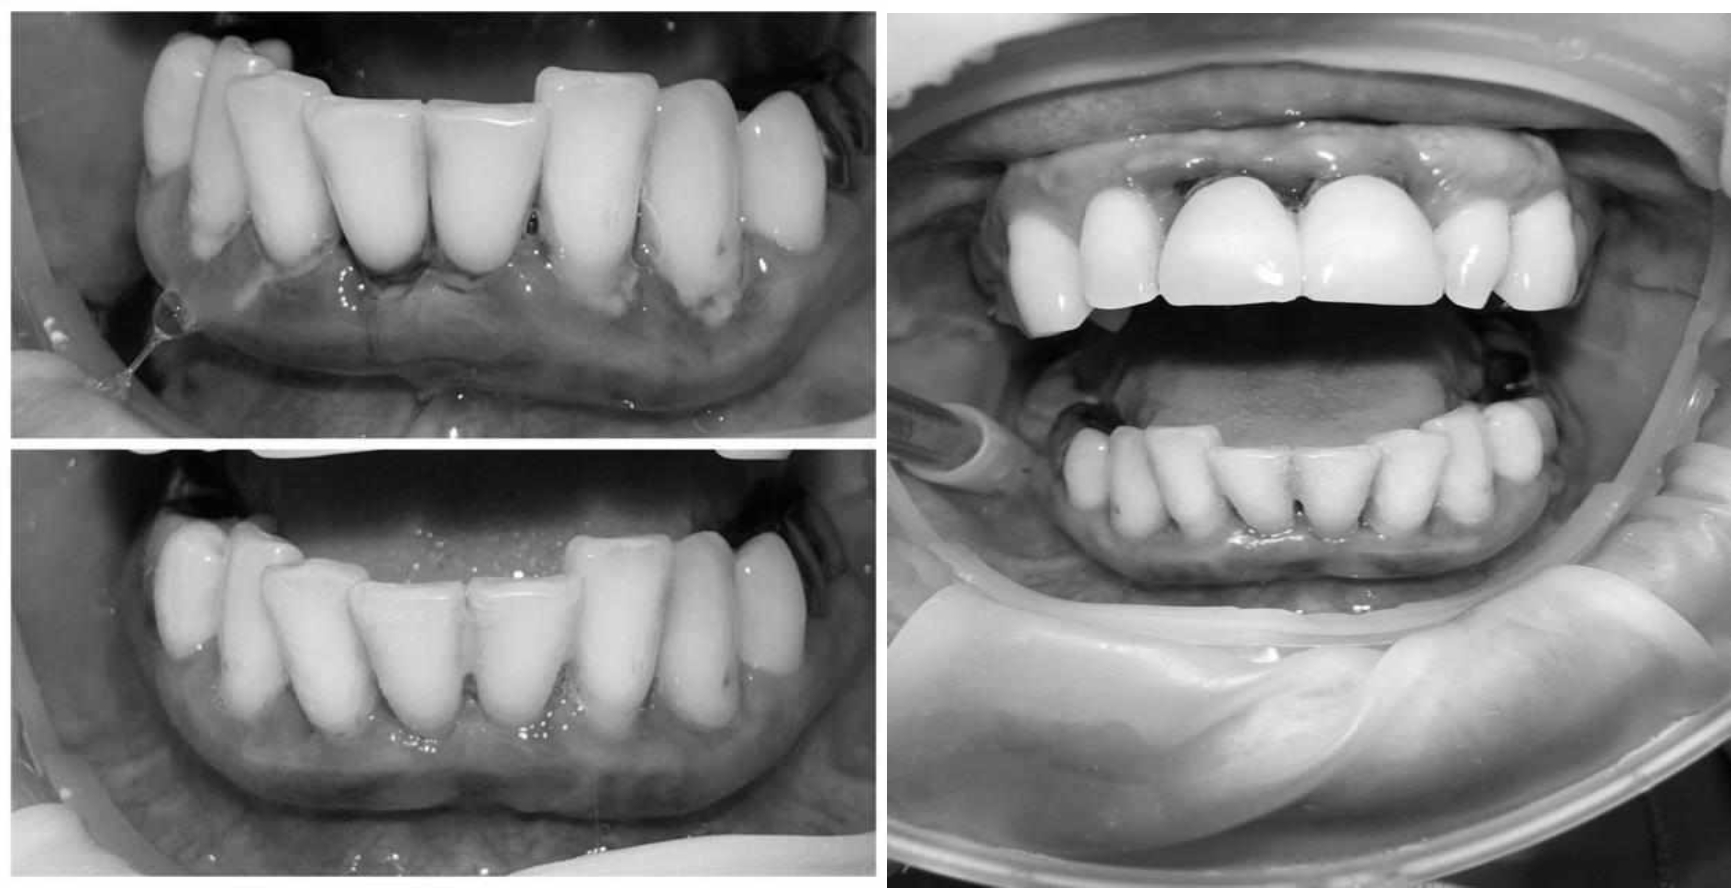

Для стабилизации пародонтологического статуса было проведено комплексное лечение, которое включало в себя: системную антибиотикотерапию, пациент был обучен гигиене полости рта, были подобраны средства индивидуальной гигиены, была проведена профессиональная гигиена полости рта с использованием ультразвукового скейлера, аппарата Air-flow, проведена поддесневая инструментальная обработка.

В качестве поддерживающего пародонтологического лечения проводилась обработка поверхности корней с применением аппарата «Вектор», диодного лазера. Для домашнего использования были подобраны ополаскиватели с содержанием хлоргексидина, рекомендованы аппликации противовоспалительных стоматологических гелей. После снятия воспалительных явлений пародонта провели шинирование 4.3, 4.2, 4.1, 3.1, 3.2, 3.3 зубов с применением стекловолоконной ленты. Контроль лечения проводился через 1, 3 и 6 месяцев.

Через 6 месяцев при осмотре выявлен удовлетворительный уровень индивидуальной гигиены, отсутствие участков кровоточивости и гноетечения (рис. 4), пародонтальные карманы уменьшились в размерах (рис. 5). Пациент отмечает значительные улучшения. После стабилизации пародонтологического статуса пациент направлен для дальнейшего ортопедического лечения.

Рис. 4. Динамика результата через 6 месяцев